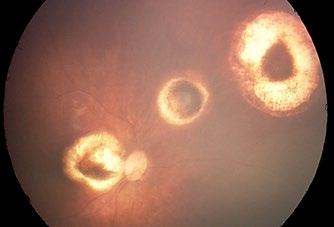

În ceea ce privește simptomele, Rb este singurul cancer pediatric care are semne clinice recunoscute, permițând astfel organizarea de campanii de conștientizare a acestei afecțiuni care duc la reducerea timpului scurs de la observarea primelor semne clinice până la punerea diagnosticului. Leucocoria (reflexul alb pupilar, Foto 1) este primul semn în aproximativ 60% din cazuri, care la început poate să apară cu intermitență sau

doar în fotografii, iar uneori pupila nu este albă, ci este neagră, prin dezlipire totală de retină. Strabismul apare în 20% din cazuri și apare în cazurile tumorilor cu afectare maculară, cu un prognostic mai bun în ceea ce privește păstrarea globului ocular, pentru că de obicei se pune diagnosticul mai repede. În 20% din cazuri, Rb se manifestă prin semne atipice, ca de exemplu uveite, glaucom, cataractă. În cazul sindroamelor genetice prin deleția brațului lung al cromozonului 13, se recomandă examinarea fundului de ochi (FO) la copilul asimptomatic. Din cei 31 de copii diagnosticați cu Rb din anul 2020 până în prezent în București, 57% s-au prezentat cu leucocorie, 25,8% cu strabism, 6,4% cu ochi roșu, 6,4% cu buftalmie, 3,2% diagnosticați la examen de rutină. Pe același eșantion de copii, în ceea ce privește vârsta la diagnostic, 48,5% au avut sub 12 luni, 22,5% între 12 și 24 de luni, și 29 % peste 2 ani.

Figura 1

Brahiterapia se utilizează pentru tumori de până la 10 mm diametru și 6 mm înălțime, situate la peste 3 mm de marginea discului optic sau a foveei, cele mai utilizate fiind plăcile cu iod sau ruteniu radioactiv. În România nu este posibilă brahiterapia pentru nicio tumoare intraoculară. In figurile 2 și 3 este aspectul unui Rb bilateral diagnosticat la vârsta de 10 săptămâni, iar în figurile 4 și 5 aspectul posttratament.

Până în anul 2020, în România tratamentul Rb includea CT și enucleația, celelalte tratamente locale se puteau realiza doar în centrele europene de Rb. În martie 2020, la începutul Pandemiei Covid-19, copiii nu au mai putut ajunge în Europa din cauza restricțiilor de călătorie, așa că am început să-i examinez la Spitalul de Urgențe pentru Copii “Maria Sklodowska Curie” (MS Curie) din București. Am intrat în contact cu medicii de la institutul Curie din Paris și de la Spitalul Jules-Gonin din Lausanne și periodic, prin sesiuni de telemedicină, analizam pozele realizate cu RetCam-ul pe care îl aveam în spital din anul 2015. Acest RetCam are și el povestea lui. A fost achiziționat cu ajutorul unei campanii de strângere

Figura 2

Figura 4

Figura 3

Figura 5

de fonduri organizate de către Asociația “Inima copiilor”, pentru screeningul retinopatiei de prematuritate la copiii din secția Terapie Intensivă Nou-Născuți din spital. Este un RetCam portabil de la Clarity, ieșit din fabricație la momentul actual, dar care încă funcționează impecabil. Recunosc că fără acest RetCam nu aș fi avut curajul să mă apuc de tratamentul Rb. În acea perioadă, unii copii au făcut recidive și au apărut și cazuri noi, și sub îndrumarea medicilor din Franța și Elveția am făcut primele tratamente, respectiv termoterapie transpupilară și injecție intraoculară cu Topotecan, la momentul respectiv majoritatea aparaturii medicale uilizate pentru tratament fiind de împrumut. Ulterior a fost achiziționată aparatură medicală cu ajutorul Asociației „Dăruiește Viață“, iar la momentul actual se poate efectua și crioterapia, pe lângă tratamentele deja menționate.